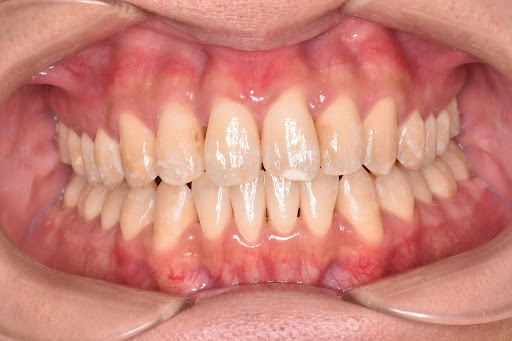

【症例写真】

ガタつきのある歯並びも、マウスピース矯正でここまできれいに整えることが可能です。

<Before>